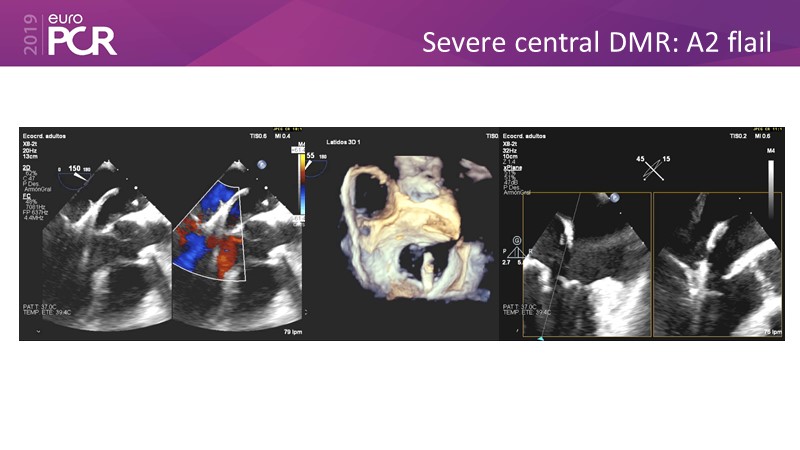

- To learn how will product innovation (Mitraclip NTR / XTR) drive improvement in procedural and clinical outcomes (EXPAND)